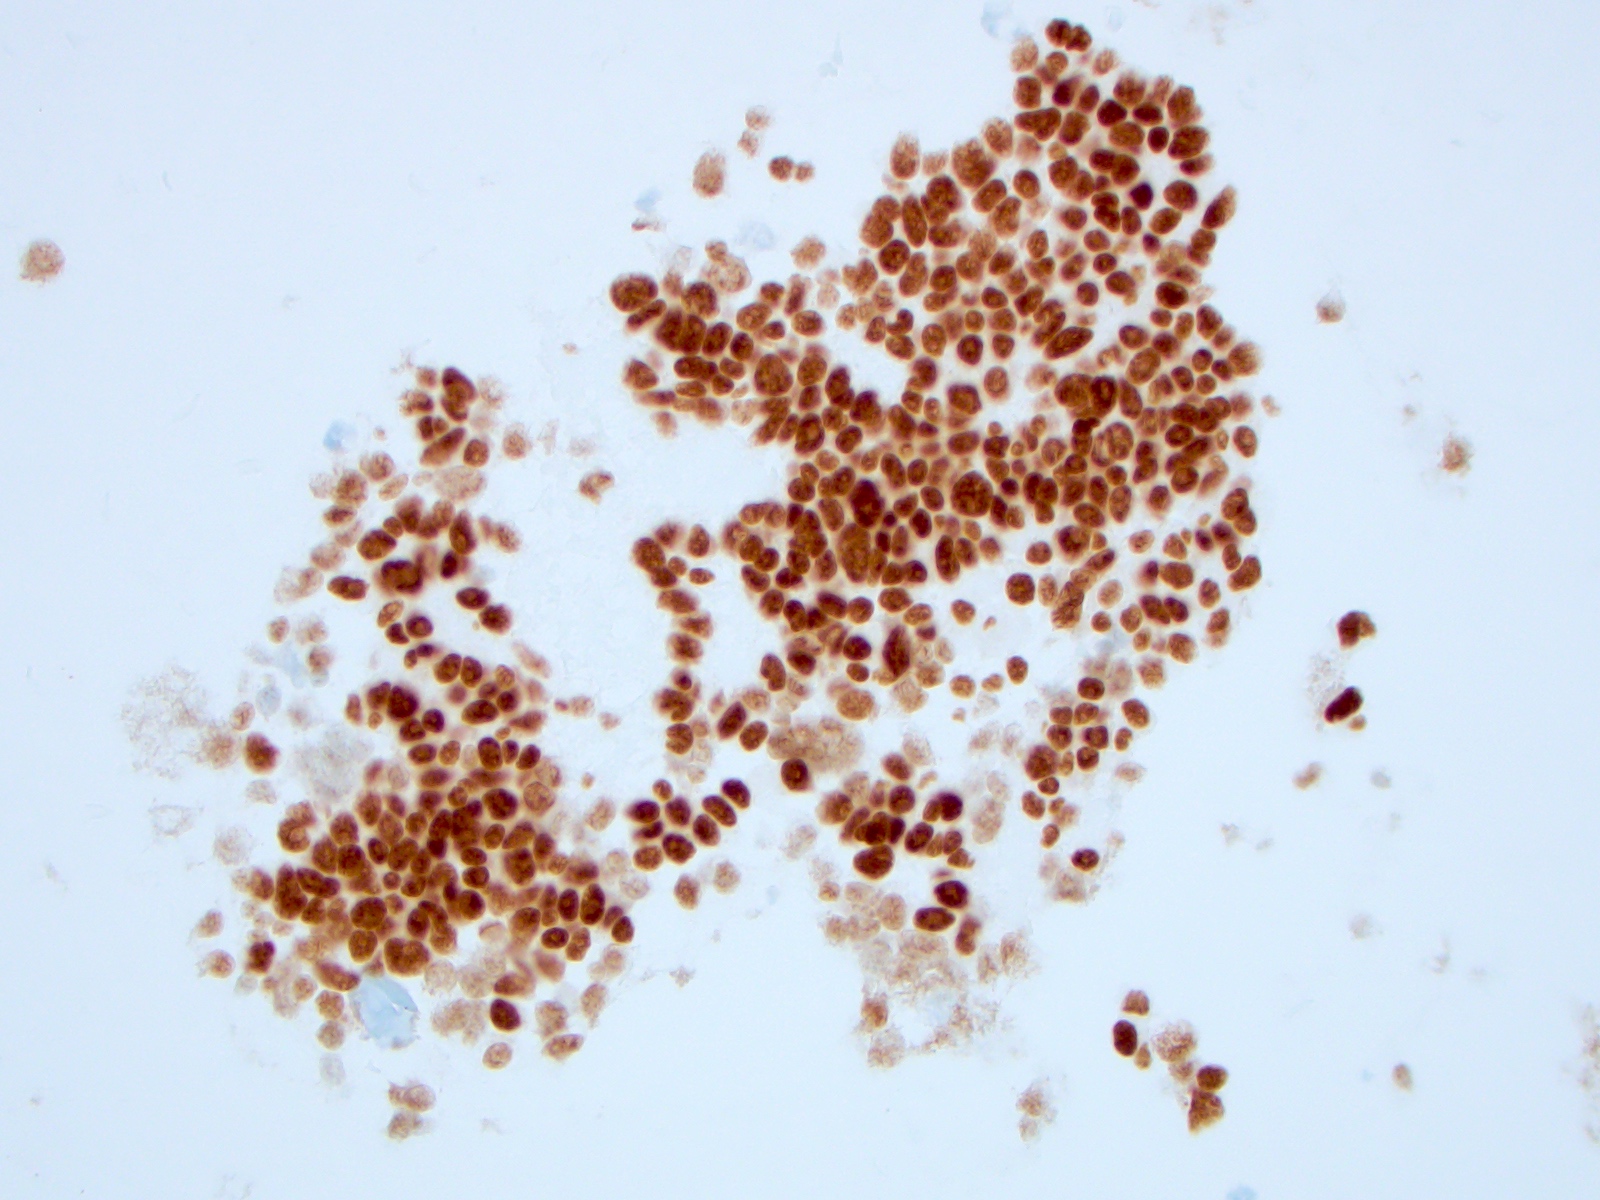

Cytology images

Contributed by Ayana Suzuki, C.T. and Shuanzeng Wei, M.D., Ph.D.

Cytology description

- Cellular specimen with round, ovoid, plasmacytoid or spindle cells singly or in small cluster; cells have abundant cytoplasm and eccentric nuclei; chromatin has salt and pepper appearance

- May have pink azurophilic granules and intranuclear pseudoinclusions; amyloid present occasionally (Am J Clin Pathol 1984;82:552)

Positive stains

- Calcitonin, CEA, TTF1 (weak to moderate), PAX8 (variable and weak) (Mod Pathol 2008;21:192), Congo red for amyloid

- Calcitonin gene related peptide, ACTH, somatostatin, gastrin releasing peptide, neurotension, low molecular weight keratin, chromogranin A and B, synaptophysin, neuron specific enolase, progesterone receptors (Mod Pathol 1996;9:68)

- Immunocytochemistry for calcitonin, CEA and thyroglobulin is useful with thin layer cytology (Appl Immunohistochem Mol Morphol 2008;16:548)